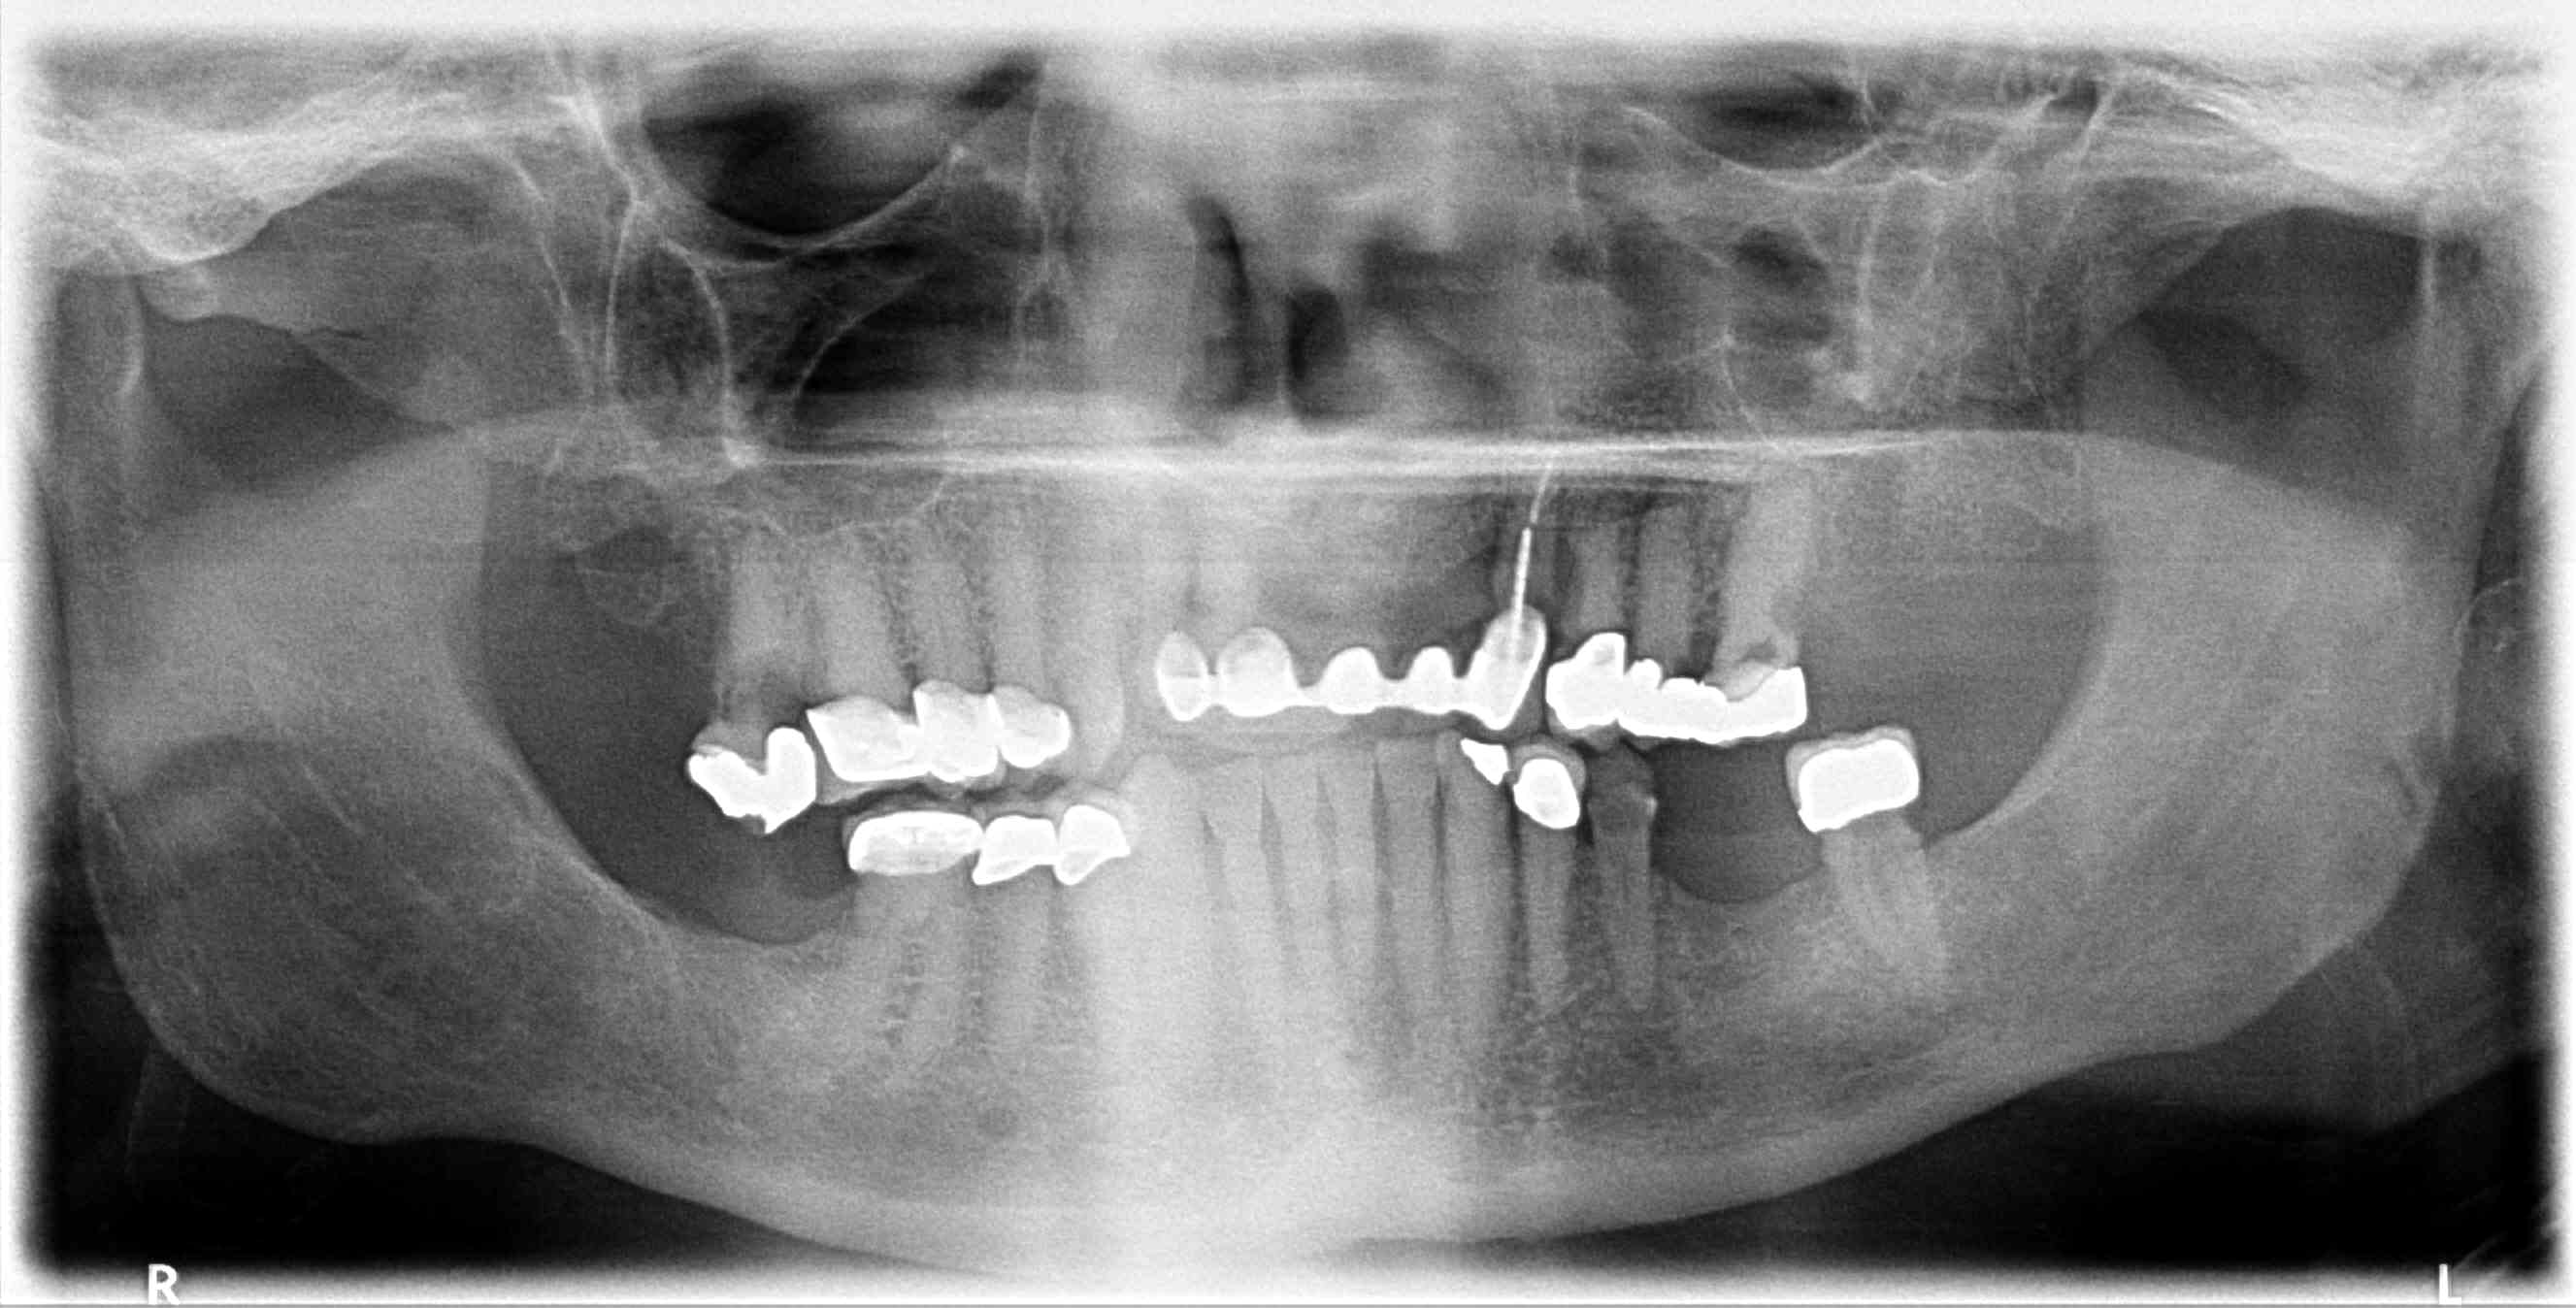

Dental Auction No. 10695: All on 4, maxillary & mandibular arches

Patient requests ALL ON 4 for both upper and lower arches, complete case fee. X-rays available, taken last week